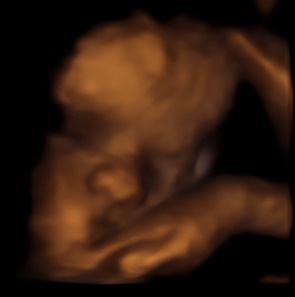

ich möchte euch noch einmal Danke sagen! Vor fast 2,5 Jahren war ich bei euch, um meinen Sohn das erste Mal so richtig zu sehen. Und wenn ich mir heute die 3D Ultraschallbilder und Videos anschaue, dann denke ich mir noch immer WOW. Und diese Erinnerung ist eine, die ich nicht vermissen möchte!

Die Ärzte machten uns wenig Hoffnung, dass er überleben würde. In dieser Zeit hatte ich noch gar nicht viele Bilder von ihm, er war ja gerade auf die Welt gekommen und jeden Abend schaute ich mir die Ultraschallbilder von ihm an, die Sie für mich gemacht hatten. Ihre Ärztin, die damals die Bilder von meinem Kind gemacht hatte, sagte mir „Sie haben ein ganz schön starkes und kräftiges Baby.“ (Ich glaube sie konnte gar nicht ahnen wie schnell sich ihre Worte bewahrheiten würden.) Und diese Worte waren für mich wie ein Mantra in dieser Zeit.

Aber es hätte auch anders laufen können und die einzigen Erinnerungen, die ich gehabt hätte, wären die Fotos gewesen, die Sie von meinem Kind während der Schwangerschaft gemacht haben. Deswegen möchte ich Ihnen noch einmal ganz herzlich und aufrichtig Danke sagen, dass sie sich soviel Zeit nehmen, diese wunderbaren Erinnerungen ein Leben lang festzuhalten.